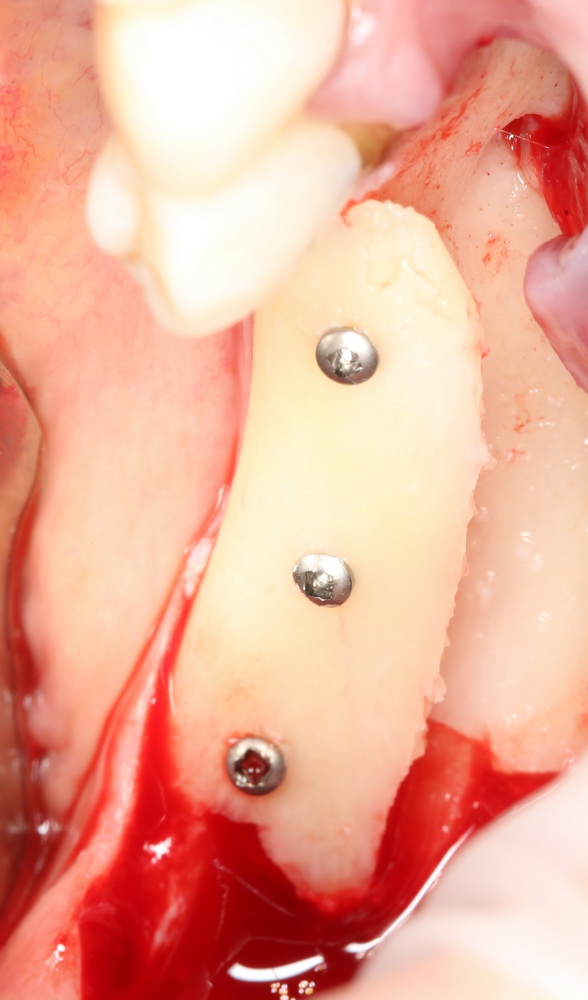

Блок готов. Делаем отверстия. Под винты диаметром 1.2 мм отверстия в блоке рассверливаются до 2.0 мм. Так сказать, для свободы действий:

А теперь просто фиксируем его с помощью винтов: